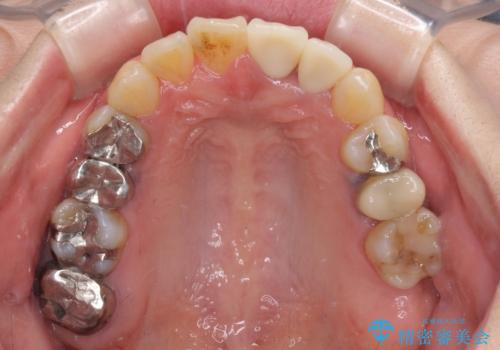

骨格的に下顎が前方位にありますが、歯列矯正で前歯の被蓋関係を改善することができると判断されたため、インビザラインにより矯正治療を行うこととしました。

また、上顎前歯と下顎大臼歯に神経を取り除いた歯があったため、矯正治療後に、セラミッククラウンにて補綴することとしました。

矯正治療中に上顎前歯が下顎前歯を乗り越える際は、前歯でしか咬めない状況が続くため、食事など不便を感じましたが、治療後には前歯の痛みもなくなり、安定した咬み合わせとなりました。